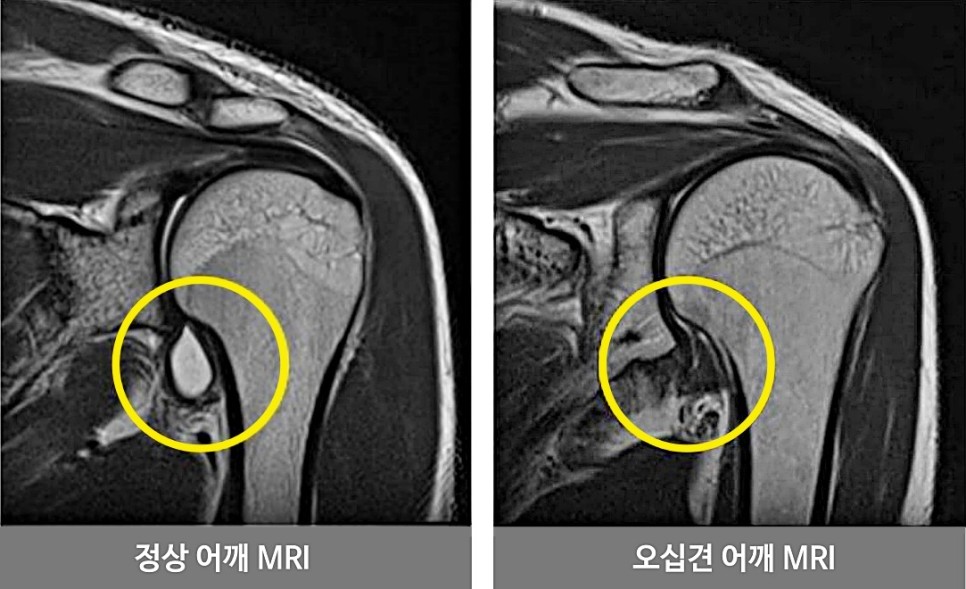

오십견이라는 게 오십대에 많이 발병하기 때문에 붙여진 이름입니다 정식 진단명은 유착성관절낭염, 동결어깨라고 하며 관절막을 형성하고 있는 관절주머니, 즉 관절낭에 염증이 생겨 유착성으로 인해 통증이나 어깨운동에 제한이 생기는 질환입니다. 발병률이 높은 연령층이 50대일 뿐이고, 실제로는 20대부터 70대까지 다양한 연령층에서 발생할 수도 있습니다.

구조적으로 특별한 원인이 없고 어깨가 뻣뻣해지는 1차성과 2차적인 원인이 있는 2차성으로 나눌 수 있습니다. 2치성 오십견의 주요 원인은 당뇨나 갑상선질환, 고지혈증 등의 기저질환을 가지고 있는 경우에 나타나기 쉬우며 회전근개파열, 석회성건염, 이두박근염, 충돌증후군 등으로 어깨 사용이 제한되어 2차적으로 어깨가 뻣뻣해지는 경우도 있습니다. 그 밖에도 골절이나 외상 등이 원인이 되는 일이 있습니다.